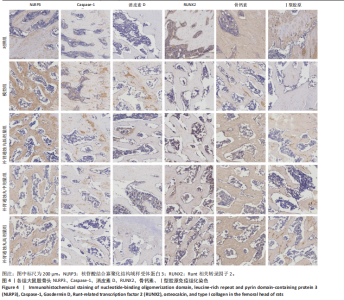

.1 实验动物数量分析 参加实验SD大鼠数量为50只,均进入结果分析。 2.2 Micro-CT检测结果 通过Micro-CT观察各组大鼠股骨头区域骨质变化,见图1。乙醇会导致大鼠股骨头软骨下骨骨量明显减少,骨小梁排列出现紊乱、稀疏等状况,而补肾通蚀丸能够改善上述情况,且呈现一定的剂量效应。模型组骨小梁厚度、骨小梁数目、骨体积分数、骨密度较对照组显著降低(P < 0.01),模型组骨小梁间隙较对照组则显著升高(P < 0.01)。经过不同剂量补肾通蚀丸干预后,各项指标均出现不同程度的逆向改变;其中,与模型组比较,补肾通蚀丸高剂量组骨小梁厚度、骨小梁数目、骨体积分数、骨密度均显著升高(P < 0.05),骨小梁间隙则显著降低(P < 0.05);与模型组比较,补肾通蚀丸中剂量组骨体积分数、骨密度显著升高(P < 0.05),骨小梁间隙则显著降低(P < 0.05);而补肾通蚀丸低剂量组仅在骨小梁间隙指标上较模型组显著降低(P < 0.05),见图2。 2.3 苏木精-伊红染色结果 与对照组比较,模型组大鼠股骨头出现核固缩现象,多见脂肪空泡,部分骨小梁出现断裂、变细;补肾通蚀丸低、中、高剂量组骨细胞核固缩和脂肪空泡较模型组有所减少;在整体结构方面,补肾通蚀丸低剂量组骨小梁变细现象较模型组未见明显改善,但断裂情况有所改善;而补肾通蚀丸中、高剂量组骨小梁断裂、变细情况较模型组均明显改善,见图3;在空骨陷窝率方面,模型组较对照组显著增高(P < 0.01);补肾通蚀丸中、高剂量组较模型组有所降低(P < 0.05),见图3。 2.4 免疫组化染色结果 与对照组比较,模型组NLRP3、Caspase-1、消皮素D蛋白表达明显增强,而Runt相关转录因子2、骨钙素、Ⅰ型胶原蛋白表达显著降低(P < 0.01);与模型组比较,补肾通蚀丸中、高剂量组能够显著降低NLRP3、Caspase-1、消皮素D蛋白表达,且促进Runt相关转录因子2、骨钙素、Ⅰ型胶原蛋白表达(P < 0.05),而补肾通蚀丸低剂量组骨钙素、Ⅰ型胶原蛋白表达有所上调(P < 0.05),其余指标则无明显差异(P > 0.05),见图4,5。 2.5 ELISA检测结果 与对照组比较,模型组大鼠血清中白细胞介素18和白细胞介素1β水平显著增高(P < 0.01);与模型组比较,补肾通蚀丸各剂量组大鼠血清中白细胞介素18和白细胞介素1β水平均显著降低(P < 0.01),且以一定剂量依赖方式递减,见图6。 2.6 Western blot检测结果 与对照组比较,模型组大鼠股骨头组织中NLRP3、cleaved-Caspase-1、Caspase-1、消皮素D、消皮"